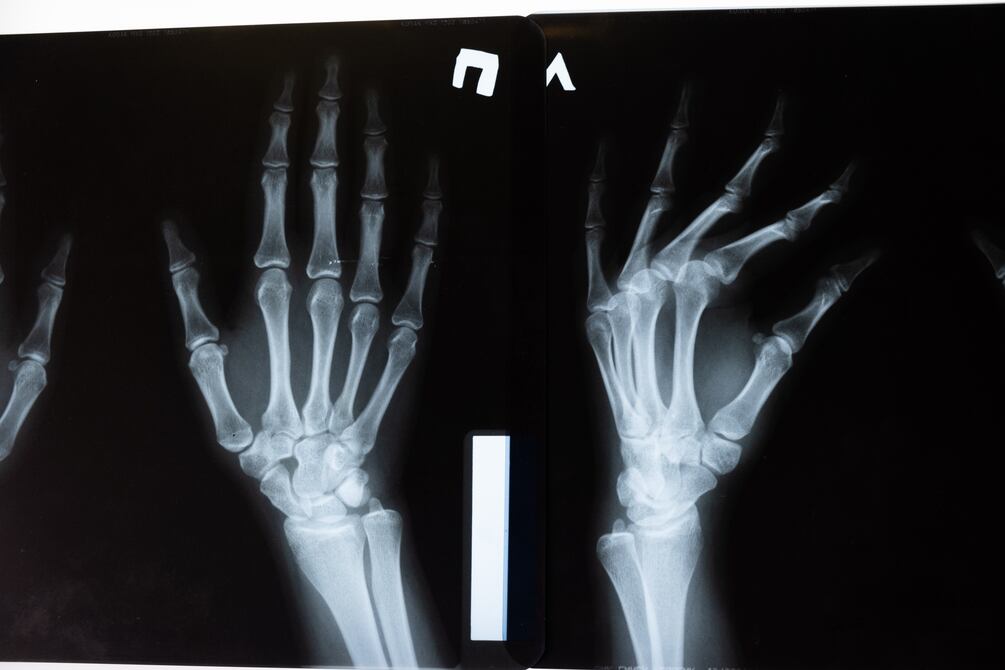

Entre las funciones de los huesos se encuentran la estabilización del cuerpo y la protección a los órganos internos. Están constituidos principalmente por tejido óseo, aunque también poseen agua; además, la médula ósea roja contenida en estos es responsable de las células sanguíneas.